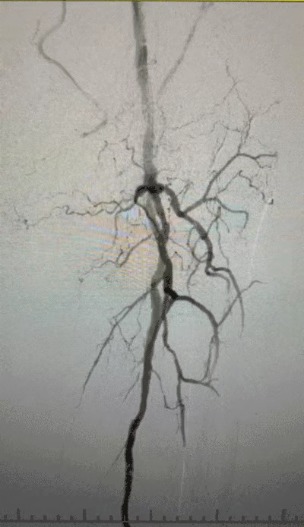

· Pencitraan preoperatif: menyebarkan stenosis parah, menyebarkan kalfikasi dalam jalan setapak anggota bawah bilateral

Prosedur pasca, stenosis arteri meningkat secara signifikan, aliran darah meningkat, dan suhu kulit mawar. Tidak ada terjadi komplikasi setelah operasi. Baik pasien maupun tim bedah sangat puas dengan hasilnya.

Kasus ini menyorot terobosan besar dalam pengobatan invasif minimal untuk arteriev anggota tubuh bawah parah, memberikan solusi yang lebih efektif untuk kasus yang menantang.